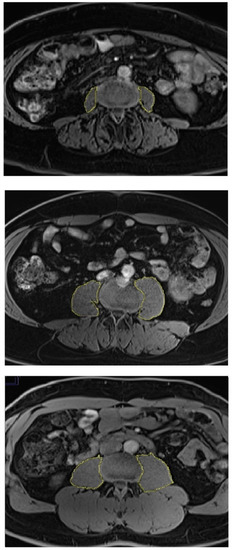

Abdominal MR scans were performed in all participants using 3.0 Tesla MAGNETOM Skyra® MR scanner (Siemens, Erlangen, Germany). Details of the protocol were described elsewhere [21]. PMV was calculated in cm3 by measuring the cross-sectional area of the left and right psoas major muscle from the second lumbar vertebral level to the fifth lumbar vertebral level and multiplying it by the thickness of MR slices (0.3 cm), as described in detail elsewhere [22]. Representative measurements of PMV are displayed in Figure 1. SMFD was determined from the cross-sectional area (in pixels) of the left and right paraspinous muscles (i.e., iliocostalis, longissimus, and multifidus) at the lower endplate of the third lumbar vertebra (total paraspinous area), as described in detail elsewhere [23]. Representative measurements of SMFD are displayed in Figure 2.

Figure 2.

Skeletal muscle fat deposition in individuals with diabetes (upper panel), prediabetes (middle panel), and normoglycemia (lower panel). Paraspinous muscles were used for skeletal muscle fat deposition measurements.